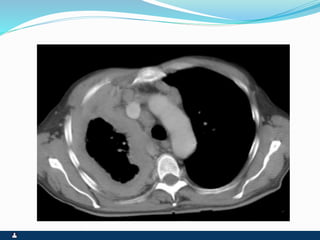

PNEUMOTÓRAX

RUPTURA DE UM DOS FOLHETOS

SINTOMAS SINAIS

 PRIMÁRIO ( ESPONTÂNEO

) SECUNDÁRIO(

TRAUMA,IATROGÊNICO )

 INÍCIO SÚBITO

 DOR PLEURÍCA INTENSA

 TOSSE SECA

 DISPNÉIA

 FACIES DE DOENÇA

AGUDA,ANSIEDADE E

SUDORESE

 EXPANSIBILIDADE REDUZIDA

 DESVIO CONTRALATERAL DO

MEDIASTINO

 ABAULAMENTO

HOMOLATERAL DOS

ESPAÇOS INTERCOSTAIS

 FTV ABOLIDO

 TIMPANISMO

 MV ABOLIDO

 RUIDOS ADVENTÍCIOS

AUSENTES

 ENFISEMA SUBCUTÂNEO

EVENTUAL